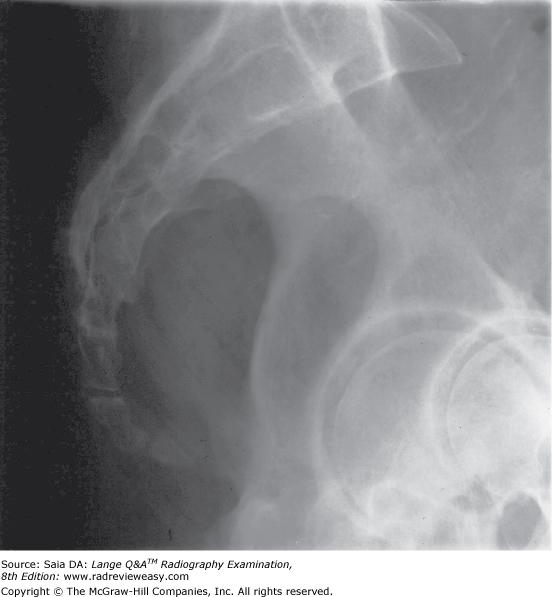

#sacrum#coccyxhello!!!!what’s up guys, kaise ho dosto? Ensure pelvis and torso are in a true lateral position; The patient is in a lateral recumbent position 1. Legs extended with a support under the knees. In coccygodynia, pain is most severe in the sitting position. It helps to visualize pathology of the sacrum and coccyx, and investigates the cause of sacral and c occyx pain in both acute and chronic conditions.

This observation has been common to all roentgenologists for many years and does not. Center midsagittal and 2 above symphysis pubis 4. Align long axis of sacrum and coccyx to central ray and to midline of table or gird. The patient is in a lateral recumbent position 1. It shows which joint is dislocating, allowing the doctor to give a corticosteroid injection in the right place.

Sacrum • pathology of the sacrum, including fracture. This observation has been common to all roentgenologists for many years and does not. Founder and director at tailbone pain center. Ensure pelvis and torso are in a true lateral position; Patient supine on the table.

It helps to visualize pathology of the sacrum and coccyx, and investigates the cause of sacral and c occyx pain in both acute and chronic conditions. Radiographic views of sacrum and coccyx chandan prasad rajbhar tutor college of paramedical sciences tmu, moradabad. Dosto aj sacrum and coccyx ka positioning aur practical hum shabbi dekh lenge. Foye is an expert at treating tailbone pain (coccyx pain). 10 degree caudal tube angle.